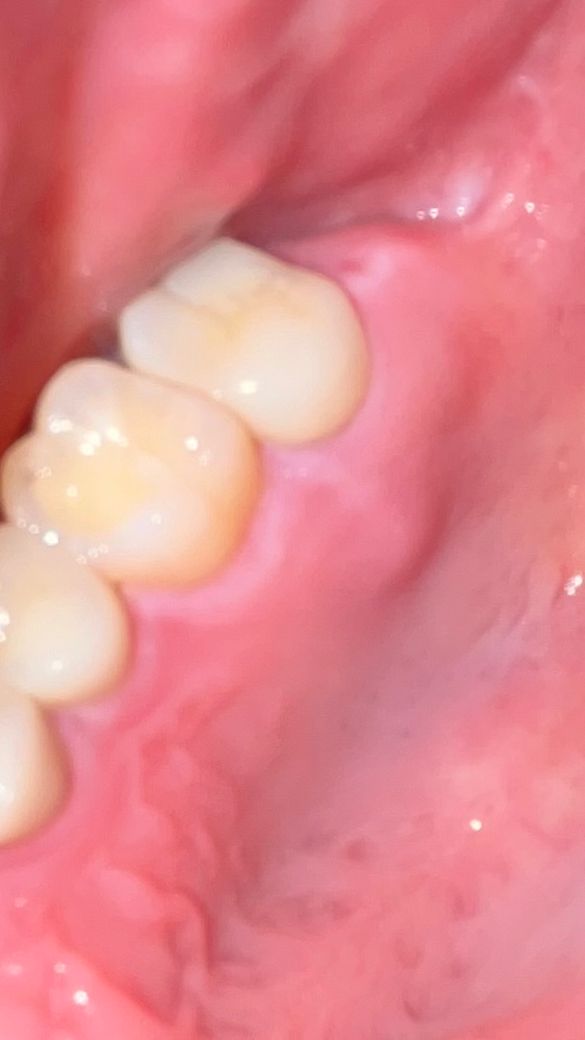

첫 번째 사진이 염증약 처방 후에 사진이고

사진에 보이는 제일 안쪽 어금니를 신경치료 후에 금니로 씌웠었고 몇 년 후 염증이 생겨서 재신경치료를 했습니다. 후에 금말고 레진(정확하게 모르겠어요ㅜ)으로 씌워서 잘 지내다가 올해 2월 초에 그 앞앞 치아 충치때문에 통증이 있어서 해당 치아도 신경치료를 했습니다. 그 사이에 있는 치아도 벽이 썩어서 레진으로 떼웠고요. 치료 후에 원래 있던 통증도 사라지고 아픈 곳도 없었는데 3월 말부터 조금씩 뭔가 만져지면서 아프기 시작해서 4월 1일에 병원에 방문했습니다. 병원에서는 감기 때문일 수 있다며 염증약을 처방해줬고, 3일간 약을 먹었지만 낫지 않았습니다. 그 주 주말에 바로 코감기가 걸려서 잇몸 통증은 잊게 되었는데 어제부터 혀로 만져보니 그 전만큼 아픈 건 아니지만 혀나 손가락으로 눌러보면 분명히 통증이 있습니다. 모양도 더 부었구요..

감기등으로 면역력이 떨어지면 잇몸이 붓거나 피가 날수도 잇습니다. 사진상에 보이는건 어떤 자극에 의해서 잇몸에 상처로 인해서 나타나는거 같은데 크게 시간이 지나면 괜찮아 지실꺼 같습니다. 그쪽으로 최대한 자극이 가지 않도록 주의 해주세요.

사진 상으로는 최후방 잇몸에 생긴 염증으로 앞에 치아들과는 연관이 없어 보이지만 통증 부위가 커지고 통증이 증가하면 치과 방문하여 검사 해보는 것이 좋습니다